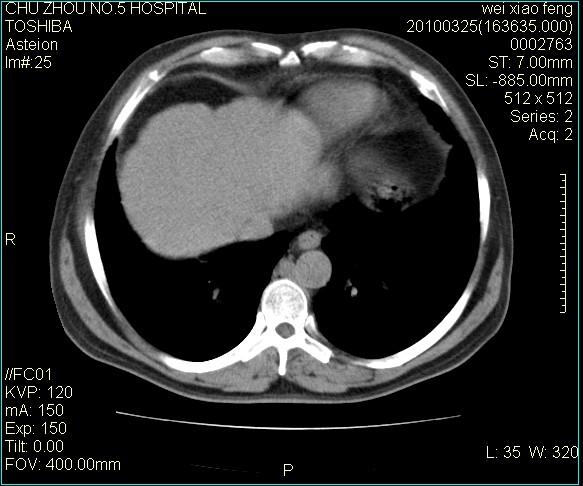

男,60岁,反复咳、痰、喘3月,加重3天。

心功能怎么样?感觉象肺淤血。

右肺中叶结节影为原发灶,考虑右肺中叶周围型肺癌并淋巴道转移